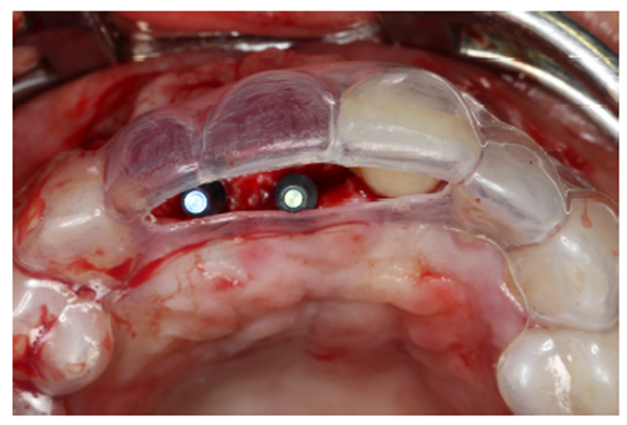

Após a descorticalização, a membrana de PTFE-d (Cytoplast) foi aberta para modelagem e adaptação no rebordo, visando o acomodamento do material de enxertia. Ela foi parafusada na cortical palatina facilitando a inserção do material via vestibular. (Figuras 5 e 6).